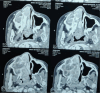

Figures